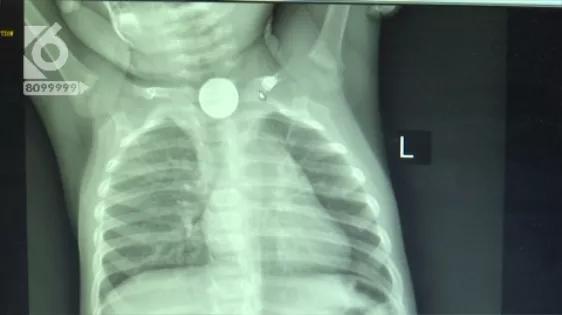

发现孩子出现了不适症状后,夫妻两赶紧带着孩子上医院,一检查才知道,孩子吞下的是一颗五毛硬币大小的纽扣电池。电池不偏不倚,刚好卡在了食管的上段。由于当地医疗条件有限,夫妻两又带着孩子赶到了昆明。

医生提供的图片可以看到,电池卡在孩子食道上,受唾液的浸泡,电池内的化学物质发生了渗漏,由于这些化学物质具有腐蚀性,虽然仅仅只是12小时,但孩子的食道已经被严重灼伤。